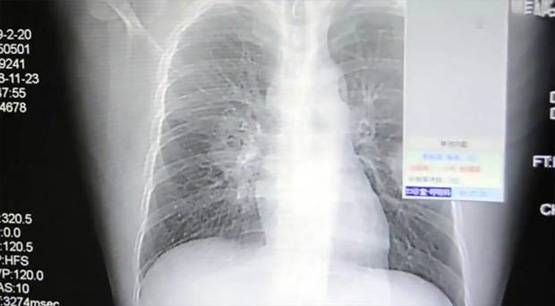

शुरुआत में डॉक्टरों के लगा कि पेंग को न्यूमोनिया है लेकिन इलाज के बाद भी उसके सिम्टम्पस दिखना जारी रहा. डॉक्टरों ने पेंग से फिर सू पूछताछ की और उसने बाद में बताया कि वह जिन मोजों को पहनता था, उन्हें सूंघता था.

फिजीशियन ने बाद में पाया कि शख्स को खतरनाक फंगल इन्फेक्शन हो चुका है. इसे पुलमोनरी फंगल डिसीज भी कहा जाता है. साइंस अलर्ट के मुताबिक, पेंग ने गंदे मोजों के फंगल स्पोर्स को सांस के जरिए अंदर ले लिया जिससे उसे इन्फेक्शन हो गया.

पल्मनोरी फंगल डिसीज या एस्पर्गिलोसिस की वजह से श्वसन प्रक्रिया पर बुरा असर पड़ता है लेकिन इसके लक्षण और परिणाम बहुत अलग-अलग होते हैं.

यह इन्फेक्शन फफूंदी की वजह से होता है. फफूंद घर के अंदर और बाहर हर जगह पाए जाते हैं. कमजोर इम्यून सिस्टम वाले लोगों पर फफूंद से होने वाले इन्फेक्शन का ज्यादा गंभीर असर पड़ता है. इन्फेक्शन के बाद सांस लेने में दिक्कत, खून वाली खांसी जैसे लक्षण सामने आते हैं.